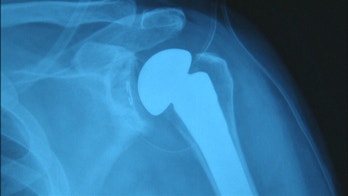

October 28, 2015 5 fixes for achy joints Don't let joint pain move you to the sidelines. Consult our guide for staying in the game